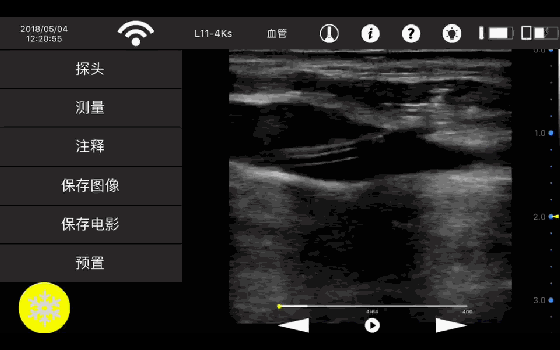

• 线阵

血管